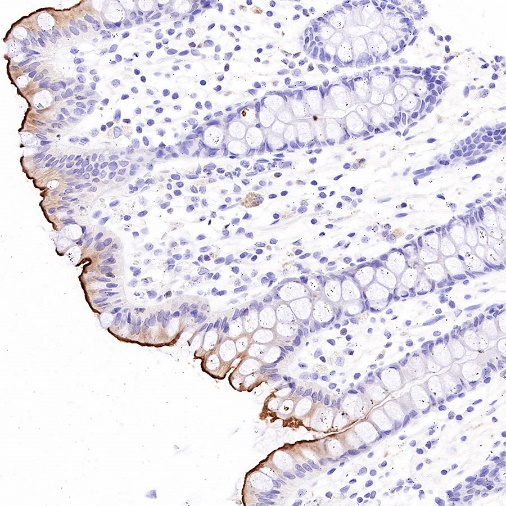

Immunohistochemistry

IHC shows positive staining in paraffin-embedded human kidney. Anti-MDR1/ABCB1 antibody was used at 1/1000 dilution, followed by a HRP Polymer for Mouse & Rabbit IgG (ready to use). Counterstained with hematoxylin. Heat mediated antigen retrieval with Tris/EDTA buffer pH9.0 was performed before commencing with IHC staining protocol.